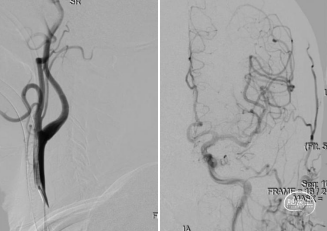

SWIM技术取栓过程:ACE 68同轴到位M1起始段,回撤Reco取栓支架同时持续ACE 68向前跟进,减少血栓逃逸的同时将血栓拉进ACE 68并撤出体外。

一次取栓实现血管再通,复查造影提示R-M1局限性狭窄,观察20分钟复查造影R-M1局限性狭窄无明显回缩,前向血流III级,因前向血流速度正常,故原位狭窄暂不同期处理,待病情稳定后择期处理。